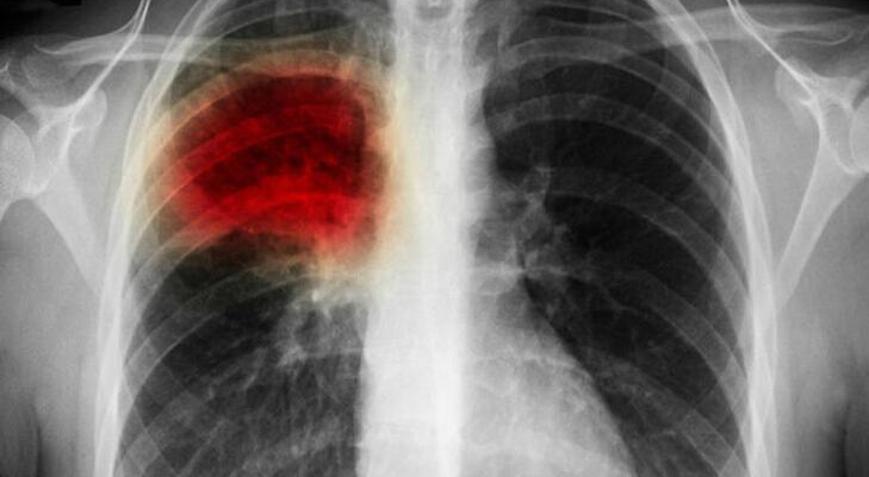

Vücudun neredeyse her organına zarar verebilen sigara, tek bir dalıyla dahi hayatınızdan 11 dakika çalıyor. Tüm bunların soluduğunuz duman ile birlikte havaya karışmasını engellemek sizin elinizde. Göğüs Hastalıkları Uzmanı Doç. Dr. Leyla Yılmaz Aydın, Akciğer Kanseri Farkındalık Ayı dolayısıyla sigaranın zararlarına dikkat çeken açıklamalarda bulundu.

İçerisinde 4 binden fazla kimyasal madde bulunan tütün ürünlerinin zararları saymakla bitmezken, dünya genelinde tütün kullanımına bağlı olarak her 6 saniyede 1 kişi hayatını kaybediyor. Göğüs Hastalıkları Uzmanı Doç. Dr. Leyla Yılmaz Aydın, “Sigara kullanımı, kanserler başta olmak üzere akciğer hastalıkları, tümör, kalp yetmezliği, damar tıkanıklığı, mide rahatsızlıkları, diyabet, üreme ve hormonal sistem bozukluğu gibi yaşam kalitesini önemli oranda düşüren hatta ölümcül sonuçlara ulaşan hastalıklara sebep olmaktadır. Öyle ki ülkemizde her yıl 100 binin üzerinde kişi tütün ve tütün ürünleri kullanımı dolayısıyla erken yaşta hayata veda etmektedir. Yapılan çalışmalar göstermiştir ki; tütün kullanımı bu şekilde devam ettiği takdirde 2030 yılına gelindiğinde dünyada tütün kullanımı nedeniyle ölen kişi sayısı yılda 8 milyonu geçecektir. ” dedi.

Doç. Dr. Leyla Yılmaz Aydın, “Tütün ve tütün ürünleri kullanan kişilerde; akciğer kanseri olma riski 22 kat, bronşit riski 10 kat, kalp hastası olma riski 3 kat, rahim ağzı kanseri riski 16 kat, prostat kanseri riski ise 2 kat fazla olmaktadır. Bununla birlikte sigara içen kişiler yalnızca kendi hayatlarını tehlikeye atmakla kalmaz, sevdiklerini de kendileriyle birlikte hastalıklara sürüklerler. Sadece 30 dakika boyunca sigara dumanına maruz kalan kişilerde kalbe giden kan oranı ciddi şekilde azalmakta, akciğerin oksijen kapasitesi düşmektedir. “Ben balkonda sigara içiyorum, kimseye zararım dokunmuyor” düşüncesi de sevdiklerinizi korumaya yetmemektedir. Saç ve giysilere sinen sigara dumanı aynı ev içerisinde yaşadığınız ya da aynı iş ortamını paylaştığınız sevdiklerinizi de pasif içici yapmaktadır.” açıklamalarında bulundu.